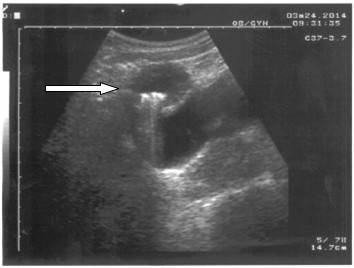

Se presentan las imágenes ultrasonográficas de una paciente femenina, de 33 años de edad, con antecedentes de salud, historia obstétrica G3 P2 A1, con esterilización quirúrgica desde hacía tres años y medio, que requirió asistencia médica por referir dolor de largo tiempo de evolución en bajo vientre, que se incrementaba a las actividades físicas y al acto sexual. Se realizó ultrasonido abdominal que mostró imagen redondeada, mixta, con calcificaciones de 38X42mm en su interior, y que desplazaba la vejiga hacia abajo, sin que se pudiera definir la causa. (Figuras 1 y 2).